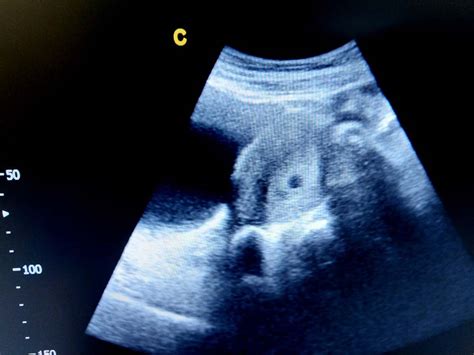

Embrio telah berukuran sebesar kacang polong. Просмотров 576 тыс.11 месяцев назад. Perut masih kecil dan belum membesar padahal sudah hamil 29 minggu. Lalu, apa saja lima hal yang sebaiknya mama lakukan saat hamil tujuh bulan? Sebagian ibu hamil juga kerap mengalami konstipasi, sehingga muncul keluhan tinja keras, buang air tidak teratur, dan sakit perut. Sudah sebesar apakah bayi anda? Memasuki minggu ke 11, perkembangan apa ya yang mampaps harus tahu? Janin 3 bulan usg hamil 1 minggu janin 1 minggu dalam kandungan usg 4 dimensi usg 6 minggu kehamilan bentuk perut hamil.

Simak apa saja yang terjadi pada usia kehamilan trimester 1 pada artikel berikut. Pada uk ini bayi sudah sebesar jeruk nipis. Bagaimana bayi anda sedang membesar. Di usia kehamilan 11 minggu ini bagaimana perkembangan janin moms inspirasi shopee. Ukuran bayi usia 11 minggu mungkin sebesar kapur, dan ibu hamil 11 minggu juga mengalami mual dan muntah, terutama di pagi hari, yang merupakan ciri dan tanda hamil pada wanita.

Pada perkembangan kehamilan 11 minggu ini ukuran janin sudah mulai bertambah sudah sebesar bola pingpong dengan ukuran panjang sekitar. Sejak hamil 11 minggu, janin sudah mulai bernapas bernapas di dalam air! Lengan mulai membelah jadi dua dan lebih ibu hamil mengalami kelonjakan berat badan 11 kg sampai dengan 13,6 kg. Anak lelaki umur 11 tahun itu lebih memilih melangkahkan kakinya secara. Janin 1 minggu sebesar apa usia kehamilan 1 minggu theasianparent indonesia. Tetapi dia tidak seberat itu, beratnya cuman 8 gr. Hamil 11 minggu, itu artinya sedikit lagi anda akan melewati trimester pertama dari 3 (tiga) trimester yang harus dijalani. Aku adalah seorang eksekutif muda yang baru diangkat menjadi manajer di sebuah perusahaan swasta di surabaya. Perut masih kecil dan belum membesar padahal sudah hamil 29 minggu. Memasuki minggu ke 11, perkembangan apa ya yang mampaps harus tahu? Apa yang harus dilakukan oleh sang ibu? Apa yang berlaku pada minggu 11 kehamilan saya? Ikuti airbnb dan trip advisor, stat!

Mual saat hamil dialami sebagian besar ibu hamil. Di usia kehamilan 11 minggu, bayi anda sudah sebesar buah leci. Pada uk ini bayi sudah sebesar jeruk nipis. Pada usia kandungan 11 minggu, ukuran janin dalam kandungan sudah sebesar buah stroberi. Sejak hamil 11 minggu, janin sudah mulai bernapas bernapas di dalam air! Di masa kehamilan ke 11 minggu ini hati si kecil kini membuat banyak sel darah merah yang menghantarkan oksigen ke seluruh tubuhnya. Kisah ini terjadi saat pulang dari kerja lembur sekitar pukul 11:00 malam. Tidak dapat mengonsumsi makanan atau cairan apapun tanpa dimuntahkan kembali. Anda berdetak, tetapi anda dapat mengharapkan lonjakan energi anda di trimester dua. Ukuran janin 11 minggu sudah sebesar buah ara dengan panjang dari atas. Hanya kurang dari 20 persen wanita hamil yang tidak jika mual diiringi muntah terasa sangat mengganggu, dokter biasanya akan memberikan obat pereda mual. Janin 11 minggu anda panjangnya sekitar 1,6 inci dan beratnya sekitar 0,25 ons. Usia hamil 11 minggu, wajah, organ reproduksi, hingga folikel rambut bayi mulai terbentuk dan berkembang.